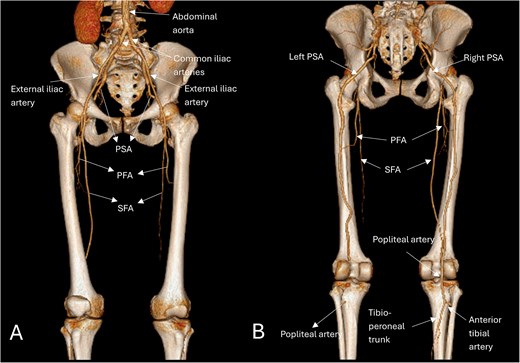

Subsequently, the patient underwent computed tomography angiography (CTA) of the lower extremities which revealed bilateral PSA (Fig. 1). The common femoral arteries trifurcated normally (Fig. 2), but the left superficial femoral artery (SFA) was significantly narrowed (Fig. 3). At the level of the knee, the right SFA joined the PSA to form the popliteal artery (Fig. 4). On the left side, the hypoplastic SFA converged with the PSA more proximally (Fig. 4); however, the artery was occluded, with no clear continuation into the popliteal artery (Fig. 4). Nevertheless, a markedly sub-occluded left popliteal artery was noted at the level of the fibular head, giving rise to a hypoplastic anterior tibial artery and tibio-peroneal trunk (Fig. 4). These findings align with Ahn-Min’s type I bilateral PSA (Fig. 5).

Three-dimensional reconstructed anatomic views anteriorly (A) show a narrowed left SFA, while the right SFA appears normal, both arising from the common femoral artery; and posteriorly (B) show the bilateral prominent PSAs as a continuation of the internal iliac arteries, the right SFA merges with the PSA as it supplies the dominant circulation of the right lower limb, the left PSA is occluded distally with no continuation into the popliteal artery; however, below the fibular head, a tibioperoneal trunk is present. Based on Ahn-min’s classification, this lower limb arterial pattern was consistent with type-I bilateral PSA.